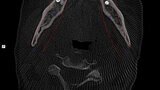

Natychmiastowa implantacja i zaopatrzenie protetyczne pacjentów z zaawansowaną chorobą przyzębia